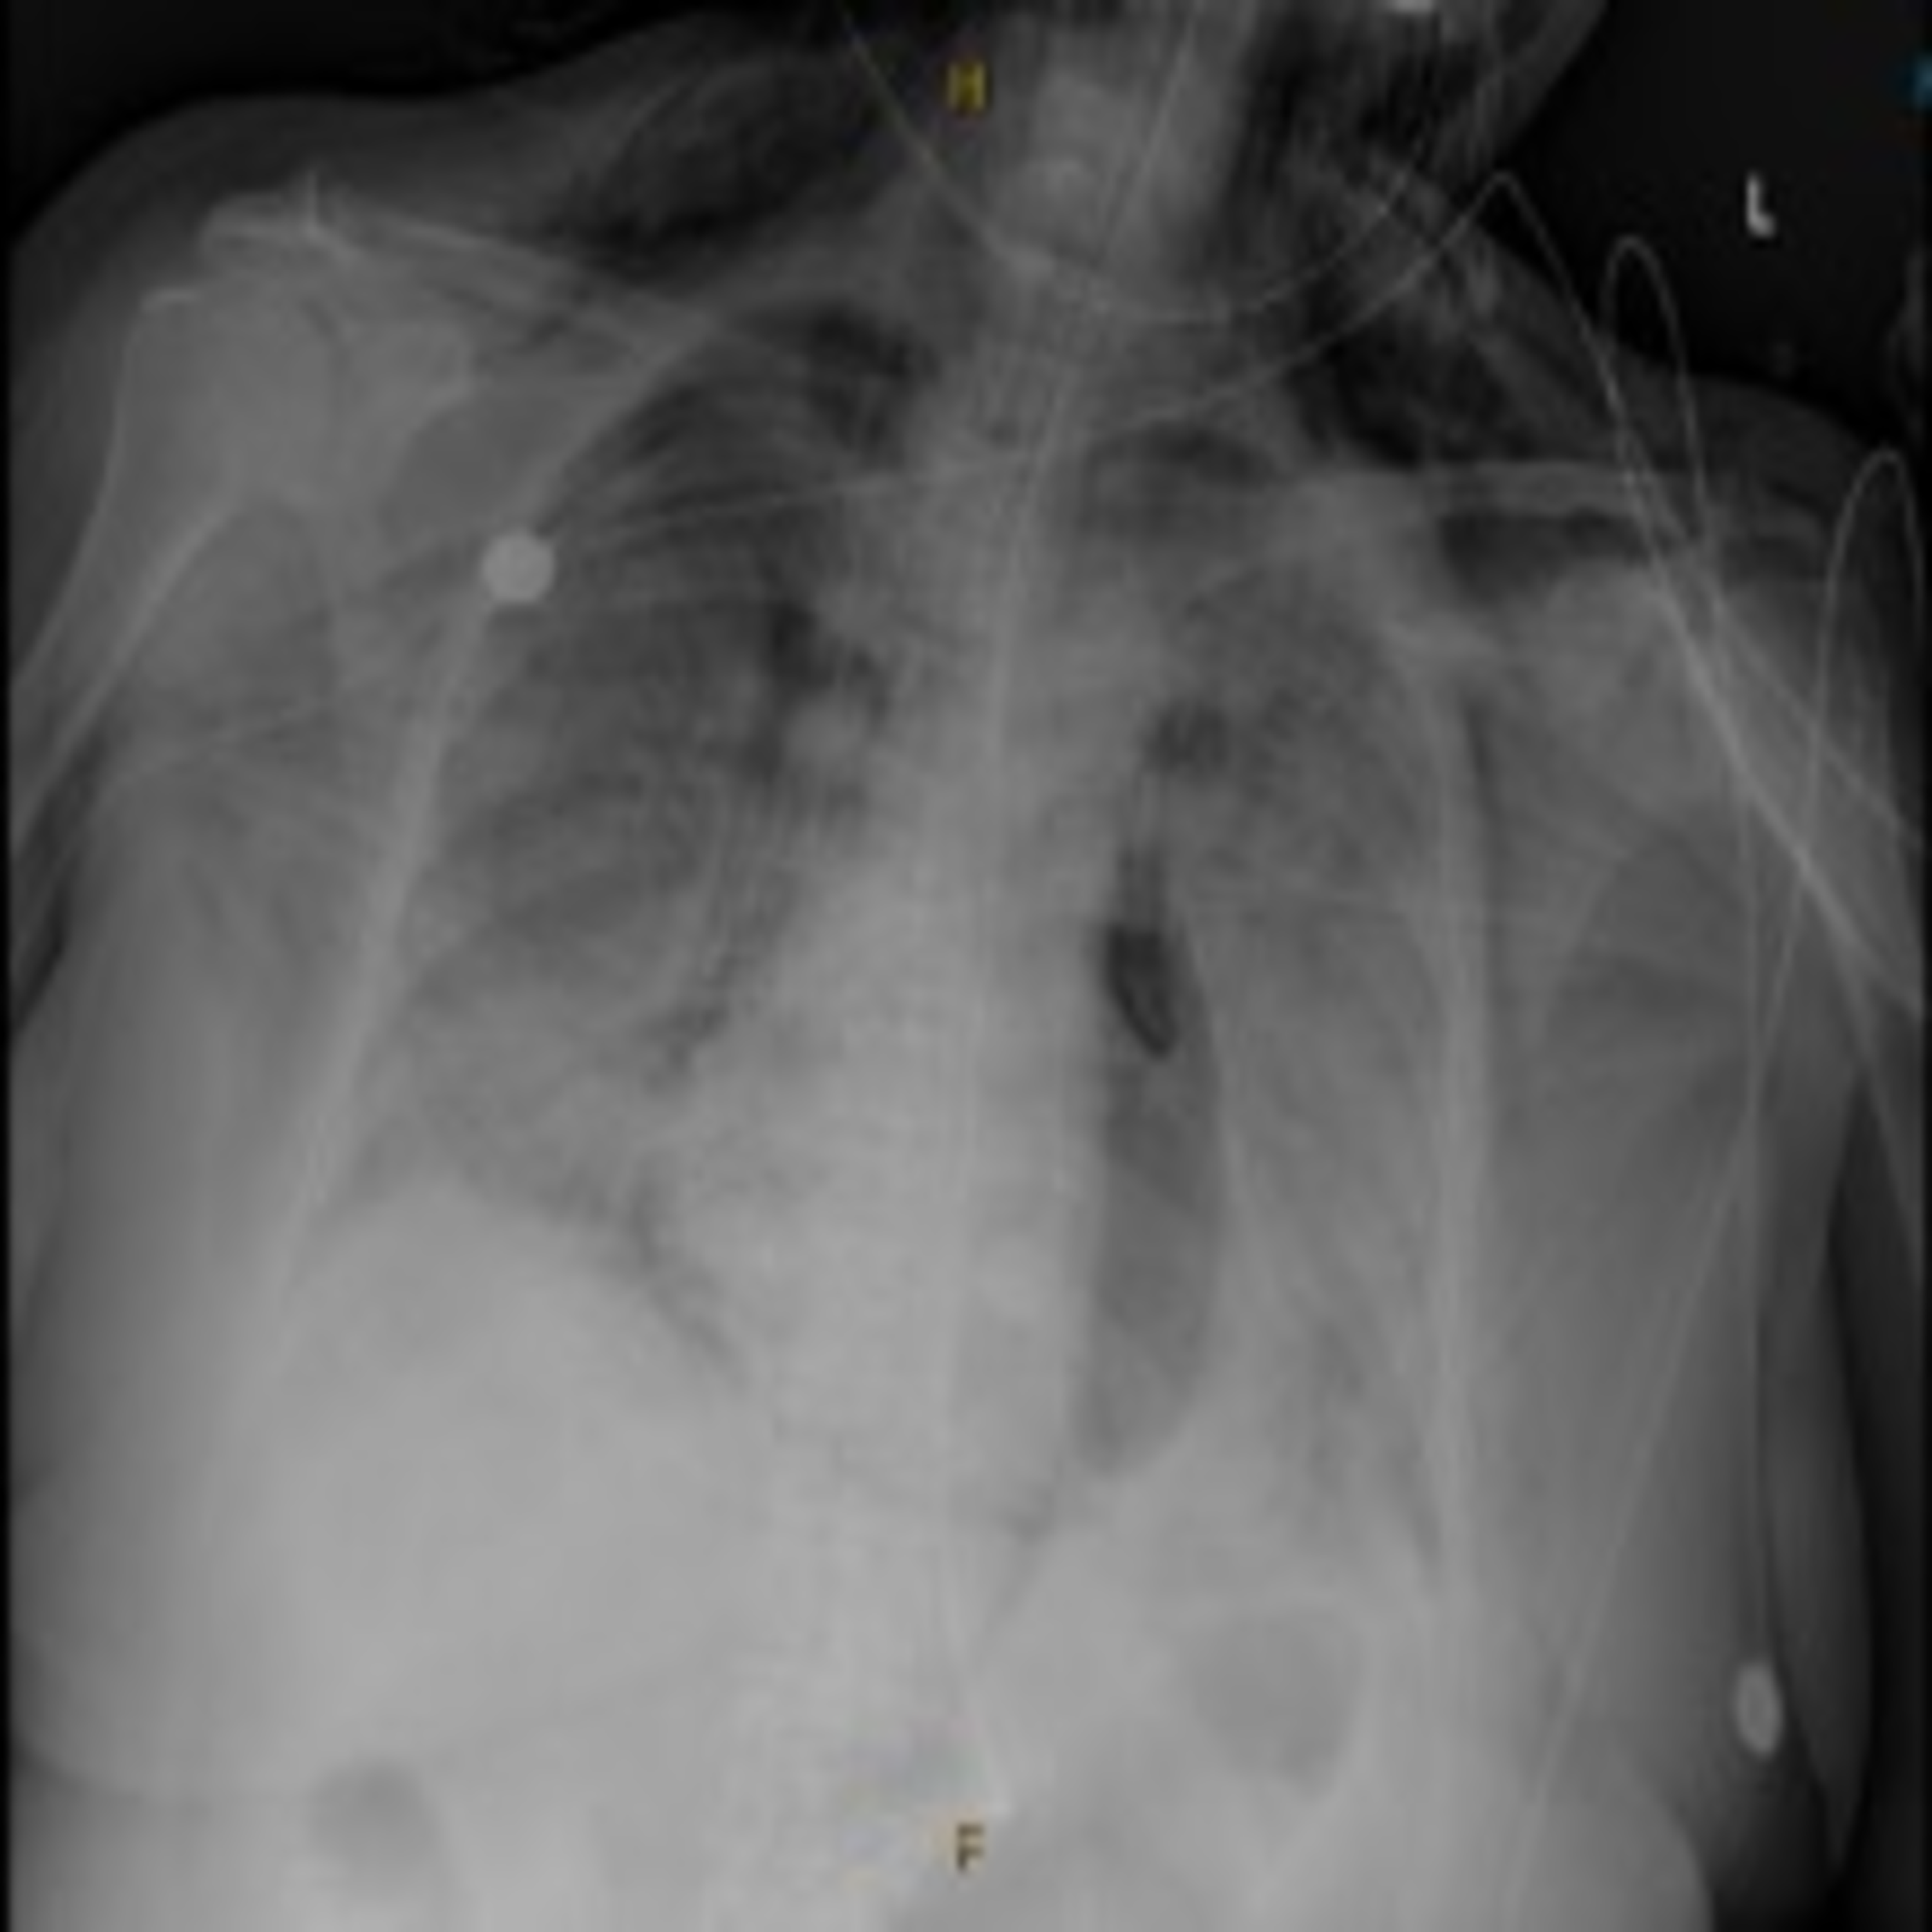

Chest Xray of patient 1, taken shortly after cardiac arrest and Post Intubation Chest X Ray It is common practice to obtain an immediate (stat) chest radiograph (cxr) upon completion of an endotracheal intubation to. In the operating room, it is not. In the operating room, it is not. Anteroposterior chest radiograph shows left tension pneumothorax after endotracheal intubation. Post Intubation Chest X Ray.